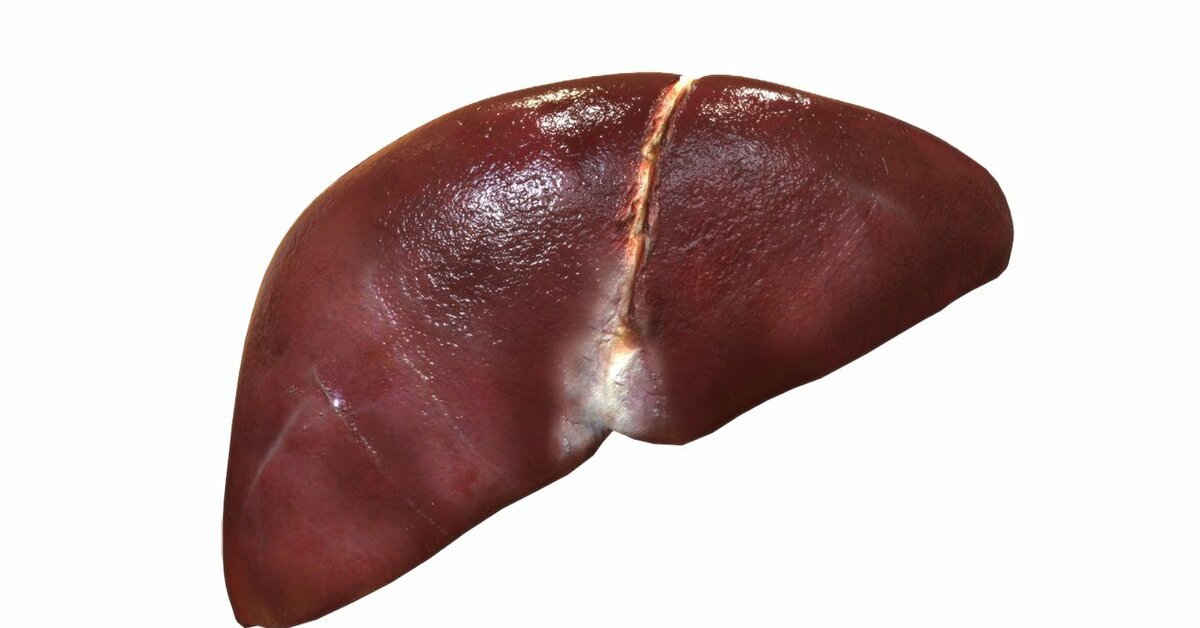

В последние годы в социальных сетях и блогах все чаще встречается необычное явление, известное как “Печень фото”. Этот термин относится к художественному стилю, при котором фотографии печени человека становятся объектом эстетического восприятия и даже искусства. Такие изображения, часто с высоким разрешением и детальной проработкой текстур, привлекают внимание не только медиков и исследователей, но и широкой публики, вызывая удивление и восхищение своей красотой и уникальностью.

Печень фото